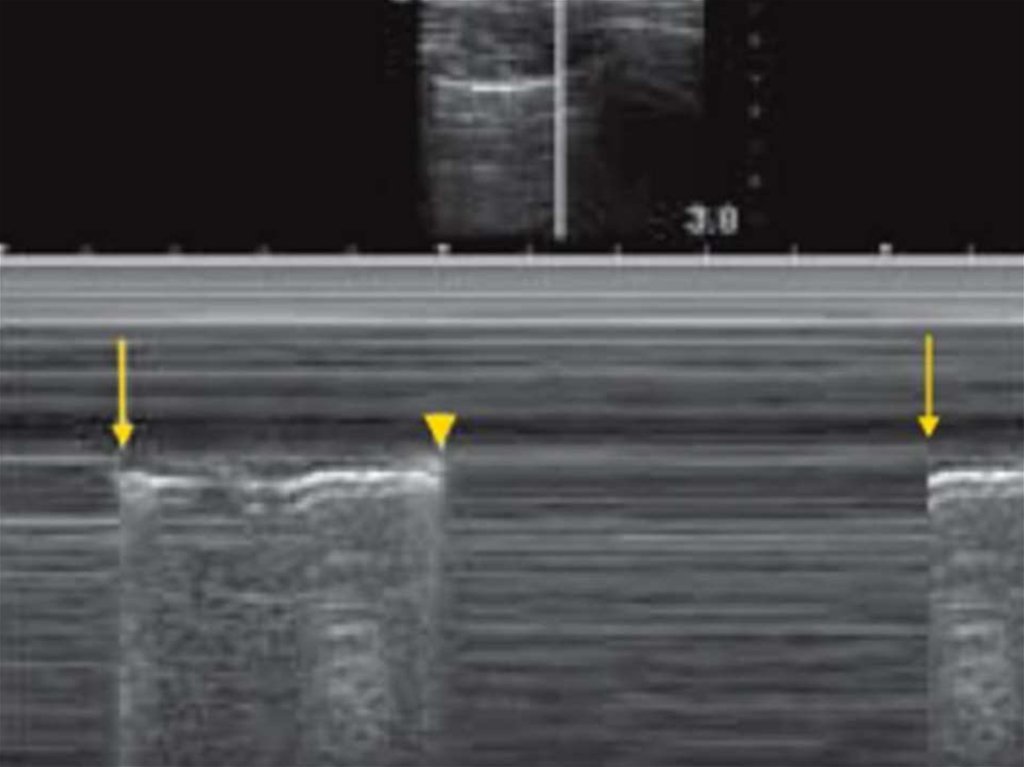

Движение свободной жидкости внутри абдоминальной полости (черные пространства)

карман Морисона